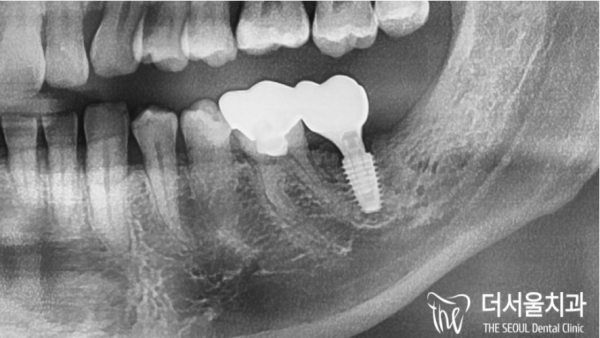

엑스레이 사진을 보면 사랑니가 누워서 인접치에 충치를 발생시켰습니다.

넓은 부위에 충치가 퍼져있어, 뿌리까지 문제가 생긴 상태로 보입니다.

미리 발치를 한다면, 앞에 인접한 치아는 문제가 없었을 것 같습니다.

If you look at the X-ray, the wisdom teeth lie down and cause cavities in the adjacent teeth.

The cavity is spread over the wide area, so it seems that there is a problem up to the root.

If you had your teeth extracted in advance, I don't think there would have been a problem with the front teeth.

치료는 이렇게 마무리 되었습니다.

주요 조직들과 가까운 위치때문에 쉬운 과정은 아니었지만

태평역치과 더서울치과에서는 안전하고 정확하게 임플란트를

심을 수 있었답니다.

The treatment ended like this.

It wasn't an easy process because of its proximity to major organizations

Taepyeong Station Dental Clinic The Seoul Dental Clinic provides safe and accurate implants

I was able to plant it.